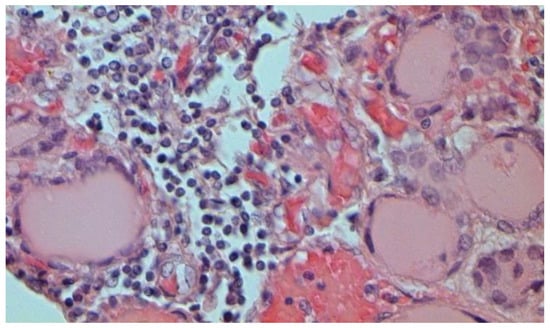

The main morphological substrate of respiratory insufficiency is diffuse alveolar damage. The term viral pneumonia, widely used in the clinic, essentially reflects its development. In turn, severe diffuse alveolar injury is synonymous with the clinical concept of “acute respiratory distress syndrome” (ARDS). In the pathogenesis of ARDS, without a doubt, the most important role is played by the damage to the microcirculatory bed, the genesis of which requires further study, but direct viral damage is most likely. COVID- 19 is characterized by a pronounced fullness of the capillaries of the interalveolar septa, as well as branches of the pulmonary arteries and veins, with erythrocyte sludge, fresh fibrin, organizing blood clots, and intrabronchial, intrabronchiolar, and intra-alveolar hemorrhages, which are a substrate for hemoptysis, as well as perivascular hemorrhages (Figure 8). Pronounced alveolar hemorrhagic syndrome is characteristic of most cases, up to the formation, in fact, of hemorrhagic infarcts (although true hemorrhagic infarcts are not uncommon). Pulmonary blood clots are important to distinguish from thromboembolism, as pulmonary embolism (PE) is also characteristic of COVID-19. Thrombosis of the pulmonary arteries sometimes progresses to the right parts of the heart, and thrombosis of the arteries of various organs with the development of their infarcts (myocardium, brain, intestines, kidneys, and spleen) is described. This distinguishes changes in the lungs in COVID-19 from those previously observed in influenza A/H1N1. Despite the pronounced hemorrhagic syndrome, significant deposits of hemosiderin are not observed.

Figure 8. Edema and perivascular hemorrhages in lung. H-E ×100.